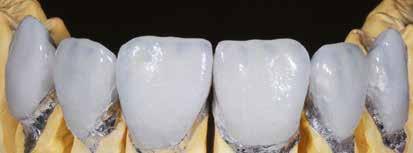

A fogszabályzó kezelések egyik legfontosabb célja, hogy elérjük a lehető legharmonikusabb interokkluzális fogérintkezéseket, továbbá az állcsont relációs helyzetének frontális és szaggitális síkban is megfelelőnek kell lennie. A fogszabályzás befejezésekor a fogpozícióknak nem orthodonciai, hanem protetikai szempontok szerint kell ideálisnak lenniük. Az Invisalign ClinCheck szoftver (Align Technology) segítségével a protetikus az orthodontussal együtt meg tudja határozni azokat a végső fogpozíciókat, amelyek a lehető legjobb végeredmény biztosításához elengedhetetlenek. Bizonyos klinikai paramétereket, mint a fogak klinikai koronájának nagyságát, az egyes fogak fogíven belüli optimális pozícióját, a fogívek egymáshoz viszonyított helyzetét, a fogak között látható rések nagyságát, a frontfogak tengelyének dőlését, az overjet és overbite mértékét már a kezelések megkezdése előtt pontosan definiálni kell. Ezeket az adatokat viszont csak a tervezett végleges fogpótlás ismeretében lehet meghatározni, ezért van szükség az orthodontus és a protetikus szoros együttműködésére.

A közös munka során az egyik legelső és legfontosabb feladat annak a meghatározása, hogy a páciens jelenlegi maximális interkuszpidációs helyzete (IKP) milyen mértékben tér el az

32 e-Journal DENTAL HÍREK

33 VII. ÉVFOLYAM – 2024. 3. SZÁM

1-4. ábra: Kiindulási állapot. 5. ábra: ClinCheck szoftverrel történő kiértékelés. A kiindulási és az orthodonciai kezelés végén elérni kívánt állapot összehasonlítása. 6-9. ábra: Az orthodonciai kezelés végén elért állapot.

10. a-c. ábra: Módosult passzív erupció jelenlétének diagnosztizálása radiológiai felvételek segítségével (altered eruption radiographic technique; AlteRx).

11. a-b. ábra: A gingivectomia és frenulectomia elvégzését követően látható állapot.

12. a-d. ábra: Az állcsont relációs helyzetét a helyreállítás befejezése után elérni kívánt állapotot bemutató mock-up felhelyezését követően rögzítettük az arcív és a harapási sánc segítségével.

állcsontok centrális relációs helyzetétől (CR). Ezt a helyzetet úgy is leírhatnánk, mint az a legideálisabb állkapocs-ízületi helyzet, amely elérését követően a lehető legkedvezőbb állkapocshelyzetből történhet meg az alsó és felső fogív végleges fogpótlásokkal történő helyreállítása. Ennek a meghatározásakor a frontális és a szaggitális síkban megfigyelhető komponenseket is figyelembe kell venni. Az optimális állcsont relációs helyzetének megállapítása előtt elengedhetetlen az állkapocs-ízület beprogramozása, a rágóizmok lazítása, és

állkapocs-ízületi rendellenességek fennállásának ellenőrzése. Amennyiben állkapocs-ízületi rendellenességeket diagnosztizálunk, úgy először gnatológiai terápiát alkalmazunk, melynek célja a rágóizmok működésének és az állkapocs-ízület egészségének helyreállítása. A komplex rehabilitációs beavatkozások kivitelezésének megtervezését csupán az új, biológiai és funkcionális szempontokból ideális állkapocs-ízületi helyzet elérését követően szabad megkezdeni.

34 e-Journal DENTAL HÍREK